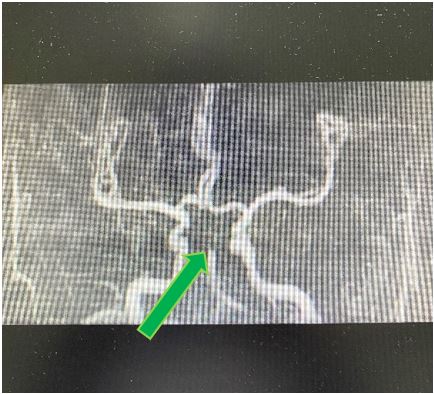

颅脑MRA示双侧大脑后动脉及双侧小脑上动脉未见显影,基底动脉远端闭塞

王虎清教授立即查看患者,与患者家属充分沟通取得同意后,神经内科介入团队其他成员范清雨主治医师、张宏医师、蒋鹏鹏护士迅速到位,导管室迅速启动,在麻醉科代志明医师的协助下为该患者进行了脑血管造影,造影证实患者基底动脉远端闭塞,同时合并右侧椎动脉闭塞,左侧椎动脉开口及V4段线样狭窄、颅内段显影不佳。神经内科介入团队医师经严谨讨论后,考虑患者目前病情危重,给予基底动脉尖负压抽吸取栓,一把完全再通,患者基底动脉血流恢复,双侧大脑后动脉及小脑上动脉显影良好。考虑患者右侧椎动脉闭塞,左侧椎动脉开口及V4段线样狭窄,仍有发生栓塞及椎基底动脉闭塞的风险,遂继续行椎动脉开口及V4段球囊扩张+支架成形术,术程顺利,手术结束时已是10月29日的凌晨。

患者术前及术后的脑血管造影DSA对比图